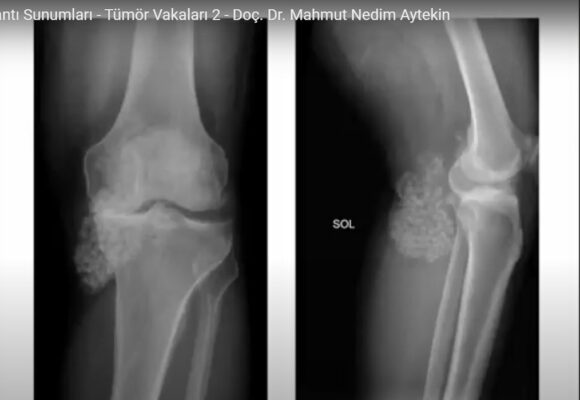

Kanserin Kemiğe Sıçraması, Sonucu Kanserli Kemik Hücreleri Tedavi Edilebilir Mi?

Bilimsel Toplantı Sunumları – Ortopedik Onkoloji’de Pet(BT ve MR) Yeri ve Sınırları